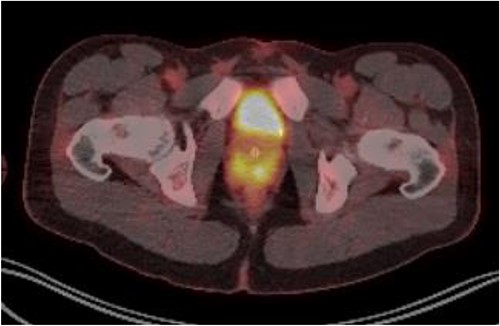

Patient was catheterised and subsequently underwent bilateral ureteric stenting. Cystoscopic views of the prostate was also abnormal and concerning for malignancy, so transperinal prostate biopsy was performed. Histology of this confirmed diffuse large B cell lymphoma. Renal function improved post ureteric stenting and patient was referred to haematology for management of DLBCL. Progress FDG PET scan (Fig. 4) 3 months post R-CHOP chemotherapy showed complete metabolic response with no avid residual lymphoma.

PET FDG scan post R-CHOP chemotherapy showing prostate with complete resolution from the disease.